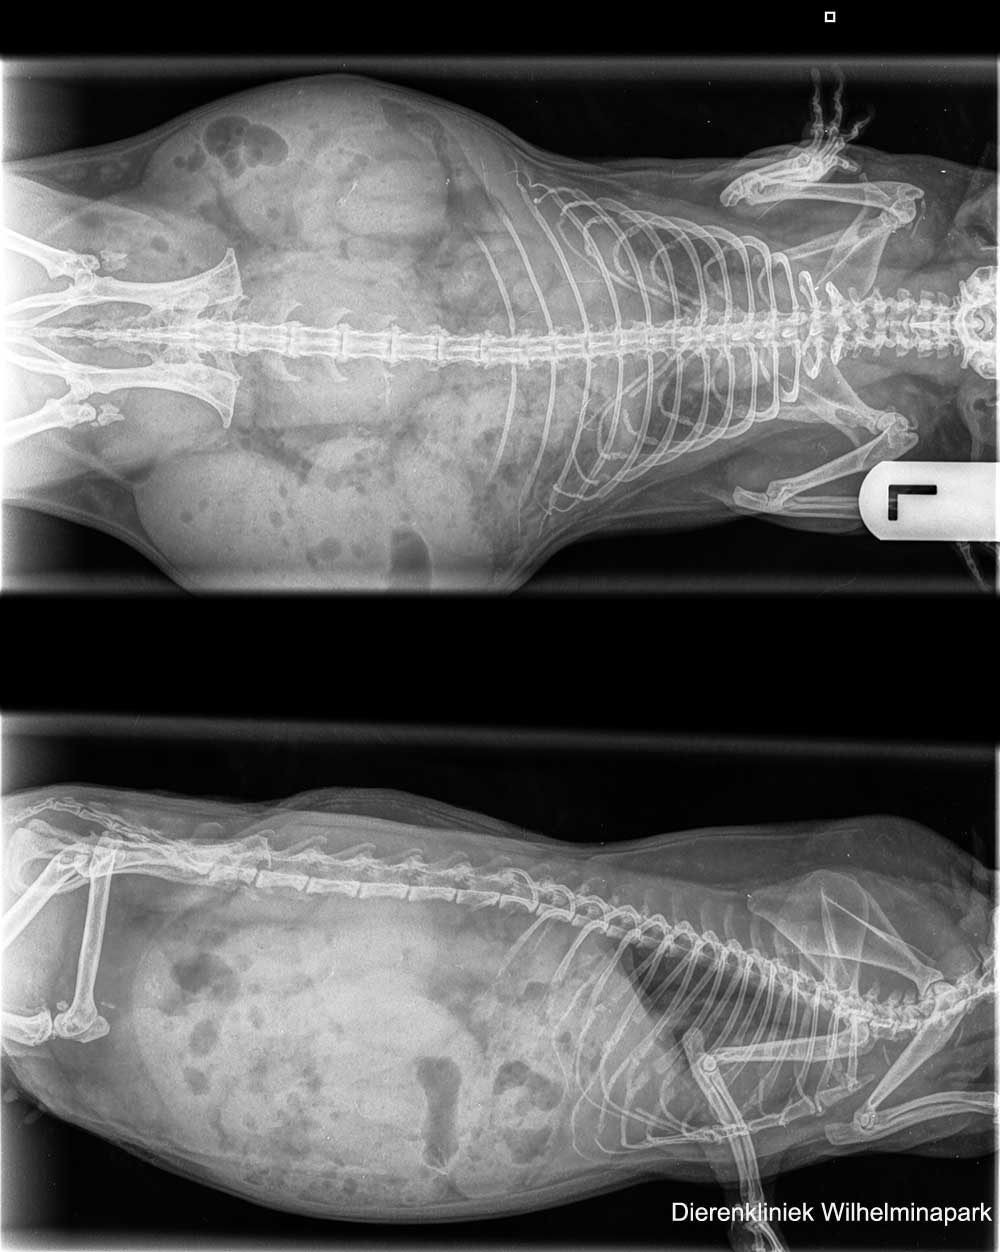

We hebben röntgenfoto's gemaakt van de borstholte.

We hebben röntgenfoto's laten beoordelen.

We hebben een echo laten maken van de borstholte. Helaas kwam er een verdenking van een tumor uit dit echografisch onderzoek.

Bij cavia June was er bloedverlies en ze was benauwd

June was een 5 jaar oude niet gesteriliseerde cavia die benauwd was, ze had een tik in de ademhaling en June had al een paar weken antibioticum gekrgen.

We hebben röntgenfoto's gemaakt van de buikholte en de borstholte.

We hebben röntgenfoto's laten beoordelen. Er komt een verdenking van tumoruitzaaiingen uit de beoordeling naar voren. June werd minder benauwd en heeft nog een jaar geleefd, ze kreeg een pijnstiller en ontstekingsremmend middel.